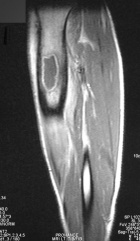

D.T. - 23 year old white male with a one month history of worsening left lower leg pain

Zoom image: Radiological image Radiological image.